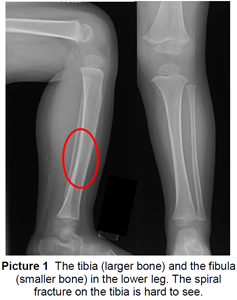

A toddler’s fracture is a common fracture in the tibia bone (large bone in the lower leg) of children usually younger than 6 years old. It is most common in children in the early years of walking – 9 months to 3 years. A toddler’s fracture is a spiral fracture of the tibia without any injury to the fibula (smaller bone in the lower leg) (Picture 1). It is a stable fracture.